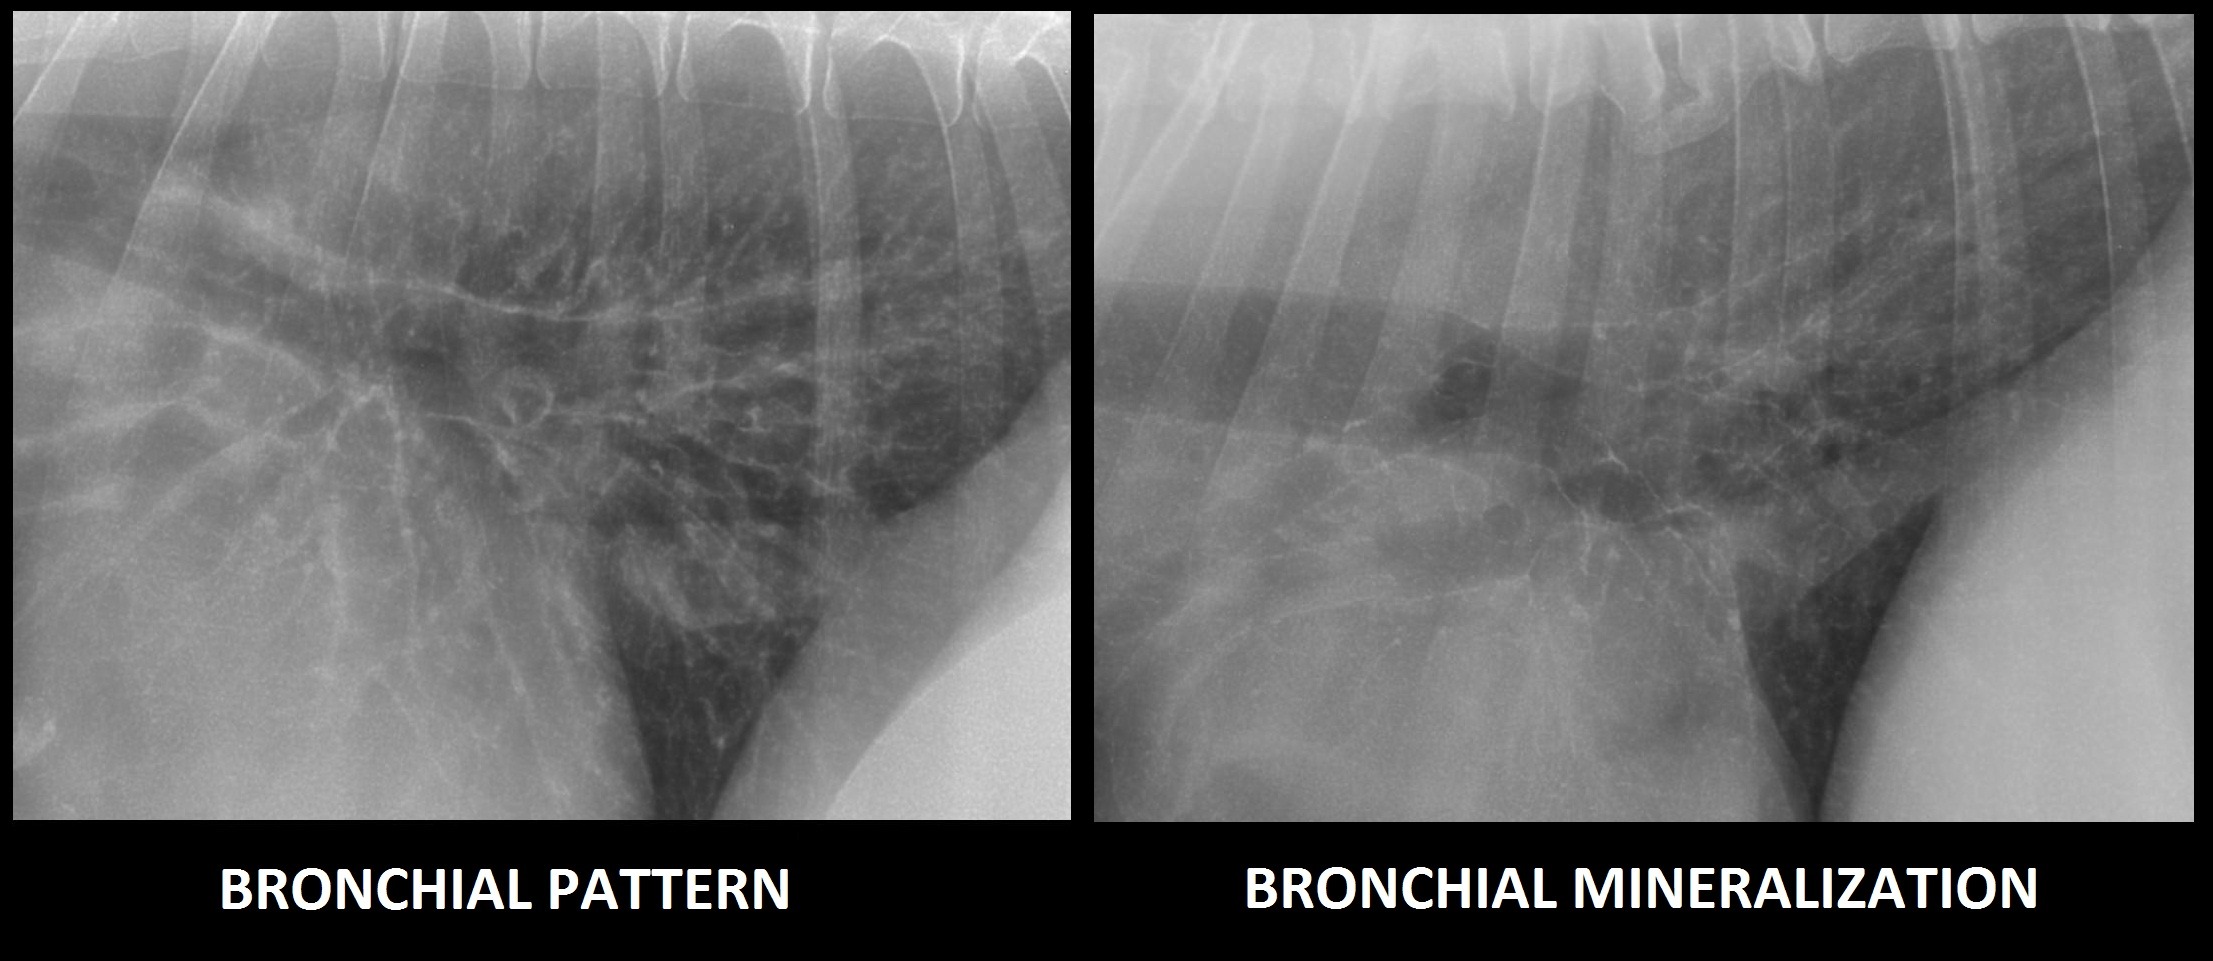

Bronchial Pattern In Dogs - Bronchial pattern is caused by thickening and increased prominence of the bronchial walls, usually secondary to chronic inflammation. Web bronchial lung pattern the bronchial pattern is obtained when the bronchial wall is infiltrated by cells or fluid or when the peribronchial space is replaced by cells or fluid. White lines indicate areas where a pleural fissure line would occur when an effusion is present. A bronchial pattern is an abnormal lung opacity caused by peribronchial cellular, fluid and fibrotic infiltration, or bronchial mucosal and submucosal. Web tracheobronchitis is a sudden or longterm inflammation of the trachea and bronchial airways; The incidence in dogs is twice that in cats;. If the cough lasts more than two months, it's generally referred to as chronic bronchitis. Kalin spasov1, michaela kunovska2, dimo dimov3. Impingement on the main stem bronchi by severe left heart enlargement; Web a bronchial pattern is diffuse thickening of the airway walls giving the appearance of thick lines and rings throughout the lungs.

It may also extend into the lungs. Web bronchial lung pattern the bronchial pattern is obtained when the bronchial wall is infiltrated by cells or.

A bronchial pattern is an abnormal lung opacity caused by peribronchial cellular, fluid and fibrotic infiltration, or bronchial mucosal and submucosal. White lines indicate areas where a pleural fissure line would occur when an effusion is present. Kalin spasov1, michaela kunovska2, dimo dimov3. Web bronchial lung pattern the bronchial pattern is obtained when the bronchial wall is infiltrated by cells or fluid or when the peribronchial space is replaced by cells or fluid.

Web A Bronchial Pattern Is Diffuse Thickening Of The Airway Walls Giving The Appearance Of Thick Lines And Rings Throughout The Lungs.